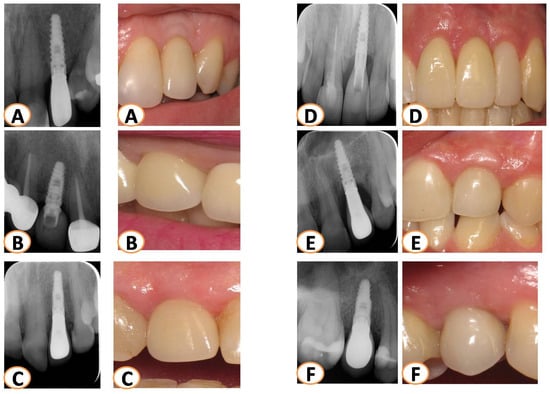

2.4. Long-Term Results of Soft Tissue Esthetic Outcome and Radiographic Evaluation

3.2. PES Assessment